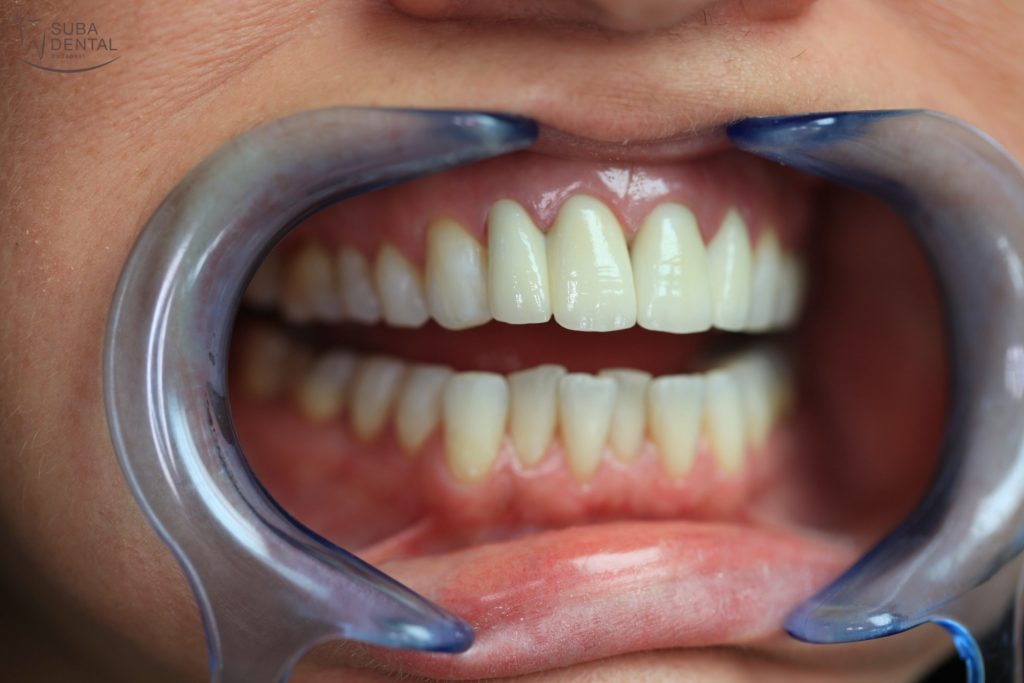

If no adjustments are required following the trial fitting of the matte teeth, the crowns are given their final glossy finish. With the permanent crowns cemented on our patient recovered his self-confidence and feels at ease to smile again.

After